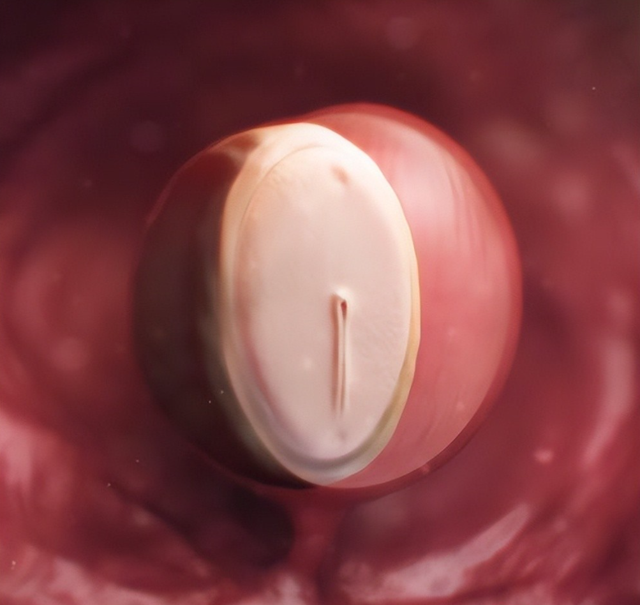

孕5周:神经发育

看到胚胎就像毛毛虫雷同,主若是先发展神经系统。